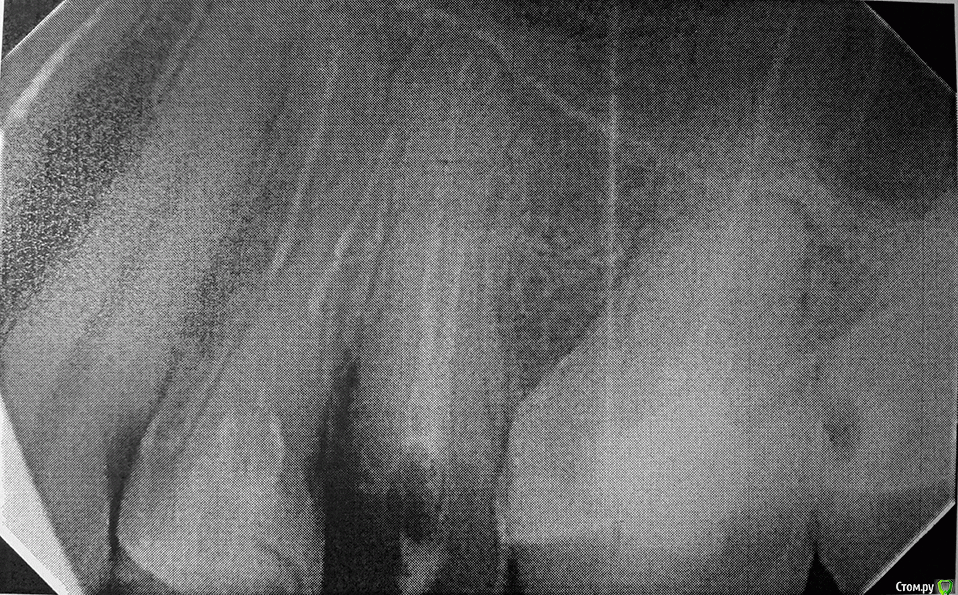

Gvozdika Опубликовано 11 февраля, 2016 Поделиться Опубликовано 11 февраля, 2016 Здравствуйте. Помогите пожалуйста принять решение: стоит ли пытаться спасать 25 зуб?История банальная: Давно стояла пломба практически во весь зуб (есть ортопантограмма как было до, сделанной год назад). Месяц назад где-то отвалилась язычная стенка под десну, еще через 2 недели - сама огромная пломба. На данный момент осталась только тонкая внешняя стенка. По результатам посещения нескольких специалистов имею 2 варианта действий:1. Культевая вкладка + коронка+перелечивание каналов (или можно обойтись без перелечивания?). Результат 50/50 и сколько эта конструкция может простоять сложно сказать.2. Смирится с потерей зуба и как следствие - имплант.Как Вы считаете? Стоит ли тратить время и деньги на первый вариант? Фото прилагаю.Спасибо за внимание. Ссылка на комментарий

___49___ Опубликовано 12 февраля, 2016 Поделиться Опубликовано 12 февраля, 2016 (изменено) скажем не "залепить " ,а "одеть остатки зубов в элегантный бронежилет ;)". ход мыслей верный. Чем меньше зубов во рту , тем чаще раскалываются оставшиеся от перегрузки, начав сейчас вы потратите меньше чем если начнете через полгода, а потратили бы еще меньше начав 1.5 месяца назад. Что касается оставить 25ый или удалить , я бы вам ответил на этот вопрос только после откидывания десны (дабы видеть уровень скола, наличие трещин) и подготовки корня под штифт...соответственно вывод напрашивается сам - идем к специалисту с желанием восстановить (при помощи культивой вкладки например) , но четко осознаем, что если во время работы доктор говорит что шансов увы нет - без какого либо сожаления удаляем (тем более вы уже готовы к этому психологически). Всегда лучше знать что ты приложил максимум усилий для того что бы спасти зуб и у тебя этого не вышло, нежели не попытавшись удалить и потом жалеть с мыслями - "а вдруг все таки можно было и спасти".п\с - качество рентген снимка (или фото) не очень. Изменено 12 февраля, 2016 пользователем ___49___ Ссылка на комментарий